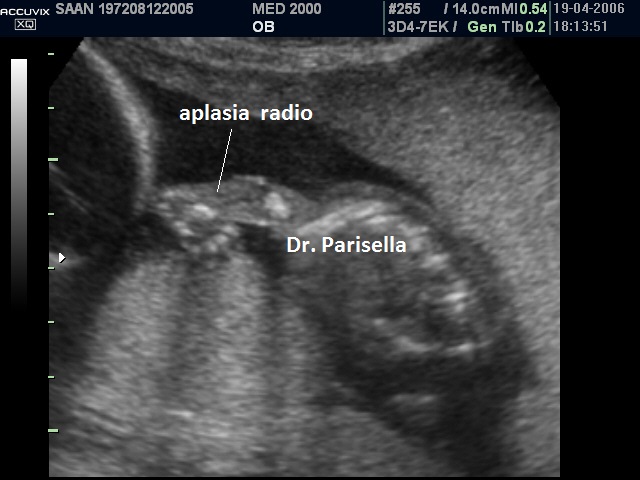

La Sindrome di Gershoni-Baruch รจ una rara malformazione congenita multipla caratterizzata da onfalocele, ernia diaframmatica, anomalie cardiovascolari e difetti radiali.